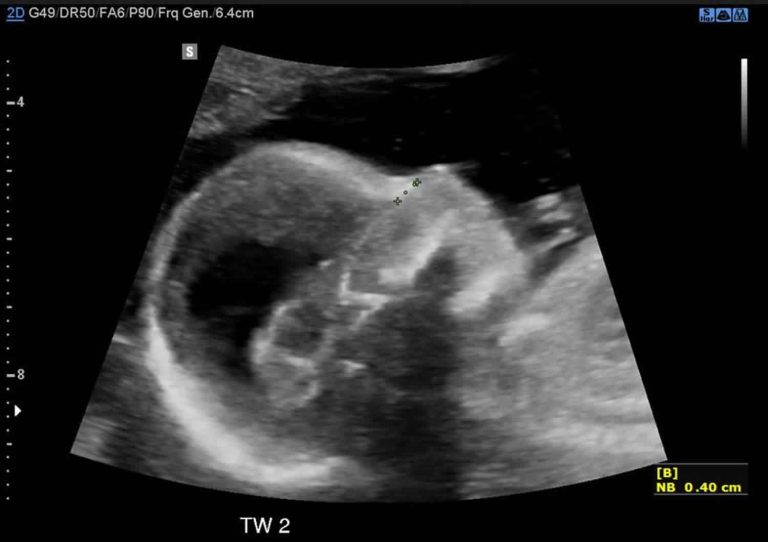

Closed neural tube defects. The figure shows different cephaloceles.... Download Scientific Neural Tube Defects Test Results  This activity reviews the role of the interprofessional team in the prevention and treatment of. Neural tube defects (ntds) are severe birth defects of the brain and spine. Ntds develop very early during pregnancy, often before you know you are pregnant. Failure to complete neurulation results in neural tube defects (ntds). A screening test performed in the pregnant. About 80. Neural Tube Defects Test Results.